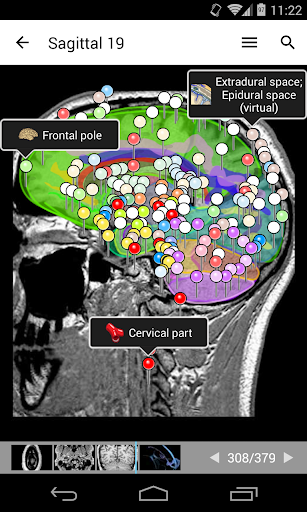

e-Anatomy tiene más de 26 000 imágenes que contienen series de imágenes en vistas axiales, coronales y sagitales, así como radiografías, angiografías, imágenes de disección, gráficos anatómicos e ilustraciones. Todas las imágenes médicas fueron etiquetadas cuidadosamente, más de 967 000 etiquetas disponibles en 12 idiomas, incluida la Terminologia Anatomica latina.

- Desplácese por los conjuntos de imágenes arrastrando el dedo

- Acerque y aleje el zoom

- Toque las etiquetas para mostrar las estructuras anatómicas

- Seleccione las etiquetas anatómicas por categoría

- Localice fácilmente las estructuras anatómicas gracias a la búsqueda de índice